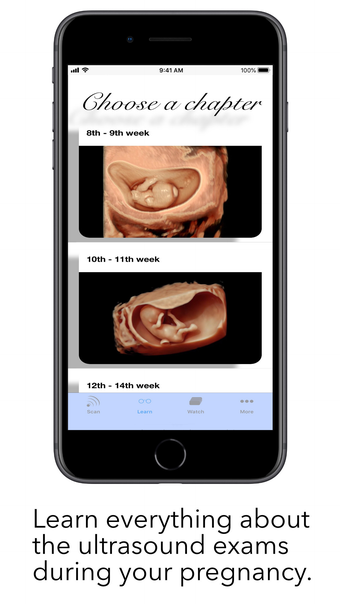

The app is divided into three different modes: Scan, Learn, and Watch. In Scan mode, users can scan a baby with labelling mode turned on to see all the important structures colored. This helps expecting parents understand the shown structures better and compare the ScanBaby image to their own ultrasound image. In Learn mode, users are taught about the developmental stages of their child through artfully crafted 3D scans of real babies that can be moved around. The scans come with labelling as well. Finally, in Watch mode, the app includes many different ultrasound videos that users might see during their own examination, with a short explanation of what can be seen.